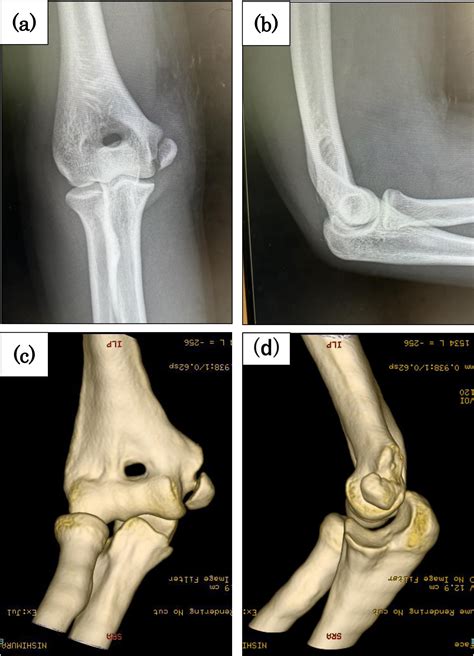

A case of pediatric medial epicondyle fracture with medial and lateral collateral ligament ...

Understand the symptoms, causes, and treatment options for a medial epicondyle fracture. Learn about effective recovery timelines, physical therapy exercises, and surgical interventions to manage this elbow injury. Discover how to safely return to sports and daily activities while preventing long-term complications with our comprehensive guide to managing medial epicondyle fractures and promoting optimal healing.